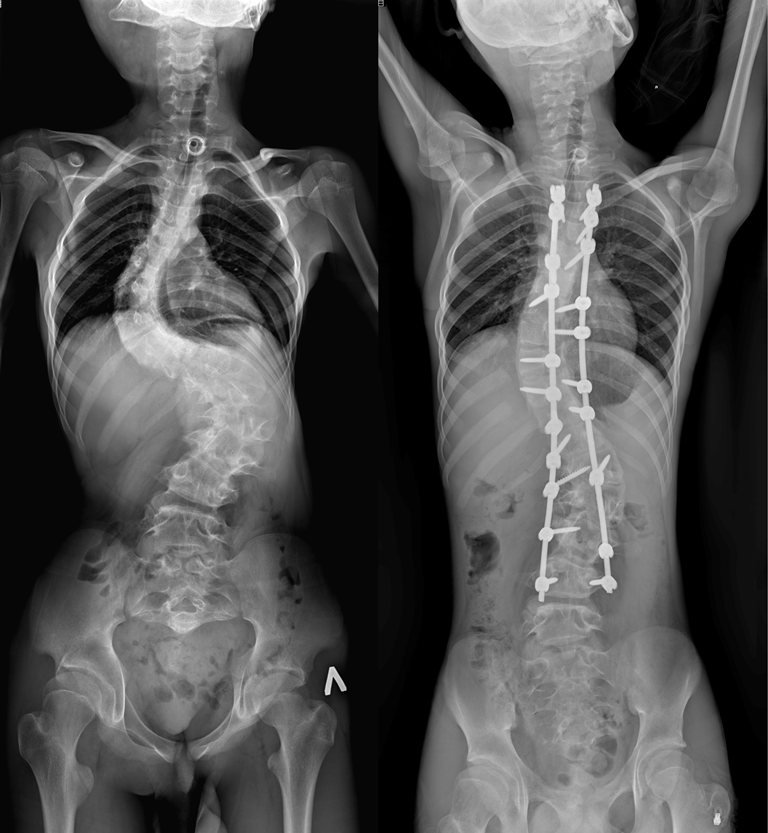

Врачи отделения травматологии и ортопедии РДКБ РНИМУ им. Н.И. Пирогова Минздрава России провели успешную операцию по коррекции кифосколиоза у пациента с синдромом Протея. Хирургическое вмешательство длилось более семи часов и было технически сложным: кифотическая деформация грудного отдела позвоночника составляла более 110 градусов, а комбинированная сколиотическая — по 90 градусов в грудном и поясничном отделах. Благодаря слаженной работе опытной команде хирургов удалось добиться существенной коррекции и обеспечить пациенту достойное качество жизни в будущем. По словам врачей, мальчик даже сможет заниматься своим любимым делом — кататься на велосипеде.

«К нам он поступил с уже существенным искривлением позвоночника, — отмечает Андрей Андреевич. — Кифотическая деформация грудного отдела составляла более 100 градусов, а сколиотическая — более 90 градусов в грудном и поясничном отделах. Отмечались нарушения походки, а совокупность этих и других проблем пациента, связанных с основным диагнозом, сильно влияла на его качество жизни».

Сложности заключались в деталях: степень деформации была тяжелой, из-за выраженных гипертрофических изменений позвонков хирургам пришлось прибегнуть к обширной остеотомии задней колонны — селективной резекции костных структур: суставов, дужек, остистых отростков позвонков. Это позволило добиться адекватной мобилизации позвоночника в области искривления. Также была проведена торакопластика, резекция трех ребер с целью достижения удовлетворительной деротации на вершине грудной клетки и улучшения возможностей адаптации органов грудной клетки в послеоперационном периоде.

Установленная металлоконструкция получилась достаточно протяжённой: от третьего грудного (Т3) по четвертый поясничный (L4) позвонок. Хирурги постарались сохранить подвижность двух сегментов в нижнепоясничном отделе, чтобы уменьшить степень ограниченности физических возможностей пациента в будущем.

После операции Мурат быстро активизировался и восстанавливался. Хирургам удалось добиться невероятных результатов в коррекции: угол кифотической деформации был снижен до 60 градусов (практически вдвое), а сколиотических — до 40-50 градусов, обеспечен удовлетворительный баланс позвоночника в сагиттальной и фронтальной плоскостях.